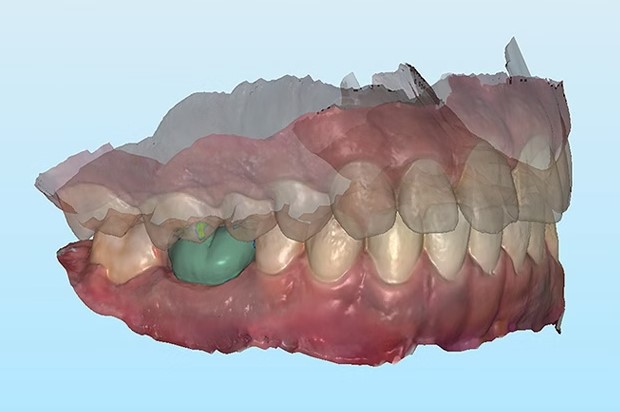

△3D打印医疗植入物

△下颌骨板的手术案例。照片来自Xilloc。

口腔癌和下颌骨重建

对于被诊断为口腔癌的患者来说,切除部分下颌骨有时是一个必要的程序。在这些情况下,下颌骨重建手术通常被用来使下面部轮廓正常化,使其重新获得结构支撑,并改善与牙齿之间的关系。该手术可以让患者在说话和咀嚼方面的功能更强大,极大地改善他们的生活质量。

为了能够进行下颌骨重建手术,下颌骨板是必要的,该装置用于对齐和稳定重建手术中的几块骨头,同时促进愈合和长期骨融合。Bernier补充说:"它不仅将改善患者的生活质量,而且由于优化、引导和个性化的手术,它还将使魁北克大学-拉瓦尔大学研究中心的3D医疗设备专业中心得到发展。我们相信,这项技术的批准只是标志着LARA 3D公司在3D医疗打印方面的创新、研究和发展的开始。“

Specifit 3D下颌骨板

加拿大卫生部于2021年9月批准了Specifit 3D下颌骨板的使用,使外科医生能够使用该植入物以及两个手术切割和钻孔指南来治疗病人。根据这项批准,3D Specifit下颌骨板必须使用生物相容性材料进行3D打印。医学专家使用23级钛来生产这款植入物,利用激光粉末床熔化(用于制备植入物)或电子束熔化(用于两个手术切割和钻孔指南)。由于该设备的设计是可定制的,因此病人特定的治疗需求将大大受益。植入物可以根据病人的解剖结构进行3D打印,这将有助于提高手术成功率,并减少手术和恢复时间。 CRIQ副总裁Lyne Dubois补充说:" LARA